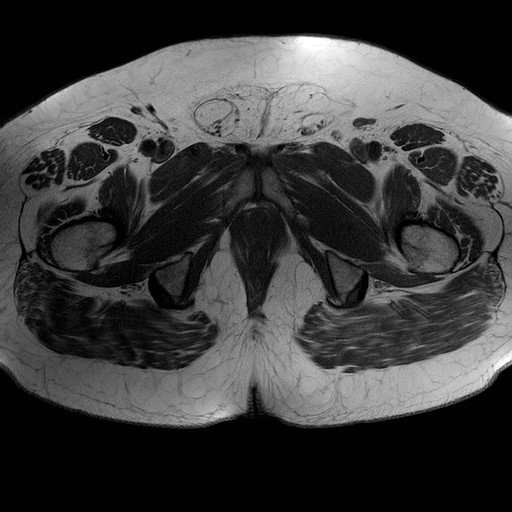

Esami: RMN BACINO

T1W_TSE

Evidenti e simmetriche alterazioni osteofitosiche in regione coxo femorale con riduzione delle rime articolari. Degenerazione completa del cercine glenoideo. Non attuali segni di versamento articolare. Non segni di edema osseo che escludono attuale algodistrofia od osteonecrosi. Lieve e simmetrica riduzione del trofismo della muscolatura glutea.